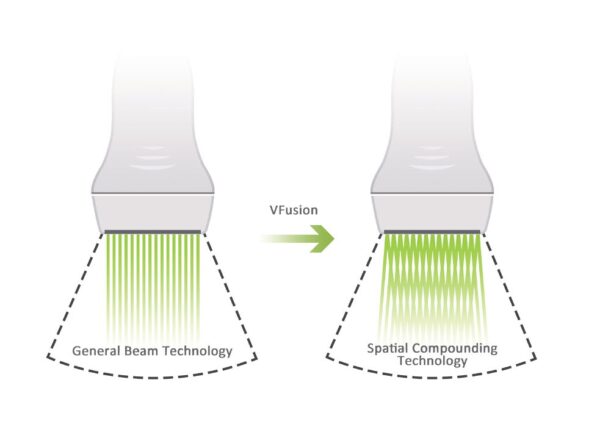

Advanced Imaging Optimization Technology